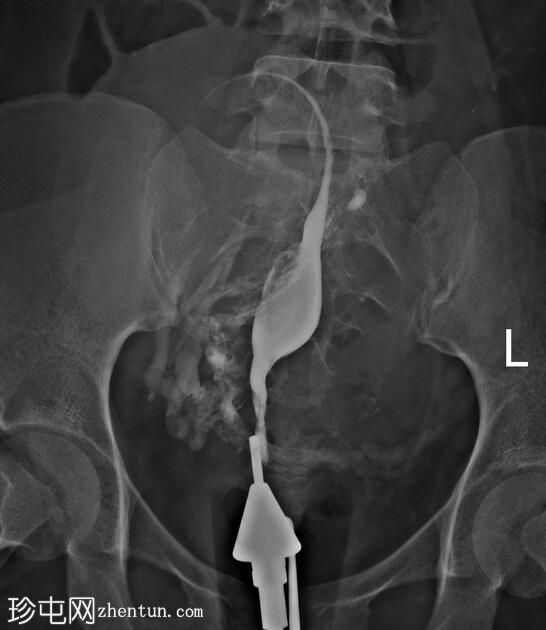

由于输卵管阻塞,左侧输卵管从远端至峡部初级段未显影。

注射更多造影剂后,造影剂渗入子宫肌层静脉和右侧性腺静脉,随后进入肾静脉。

手术开始三分钟后,造影剂进入肾脏,充盈肾盂肾盏系统,然后流入输尿管和膀胱,形成类似于静脉肾盂造影(IVP)的影像

子宫输卵管造影术中出现类似静脉肾盂造影的影像提示可能存在输卵管阻塞,这是由于造影剂流入输卵管并随后流入性腺静脉受阻所致。